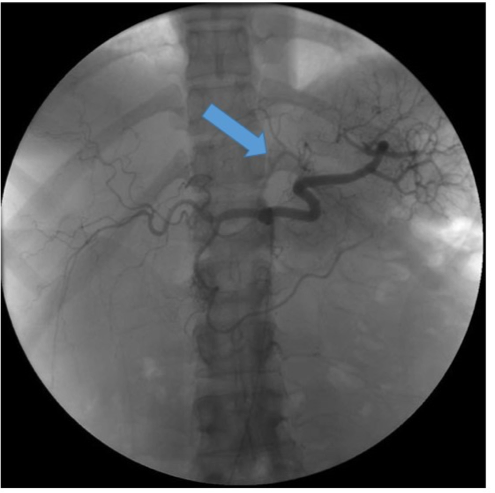

Figure. Single arteriogram image demonstrating the left gastric artery (aka “bariatric artery”), indicated by the blue arrow.